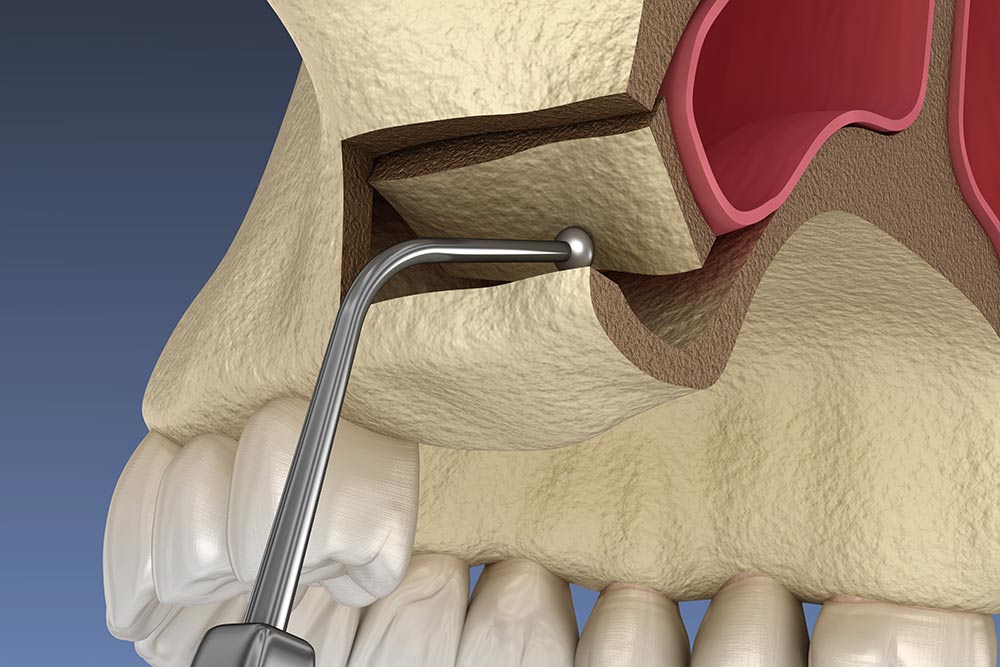

When the upper back jaw doesn’t have enough bone height to support an implant, a sinus lift (also called sinus augmentation) can help. This gentle procedure adds bone beneath the sinus to rebuild the area, making implant placement secure and long-lasting. It’s a routine, well-established treatment that allows many patients who were previously told they couldn’t have implants to enjoy a confident, complete smile again.

Guided 3D planning and minimally invasive surgical techniques help ensure the procedure is safe, precise, and as comfortable as possible.

Minor risks include sinus membrane perforation, which our experienced team minimises through advanced techniques.

Sinus lift procedures are safe, but as with any surgery, there are potential risks. These may include infection or a tear in the sinus membrane. However, with planning, advanced techniques, and the experience of our team, the chances are kept to a minimum.